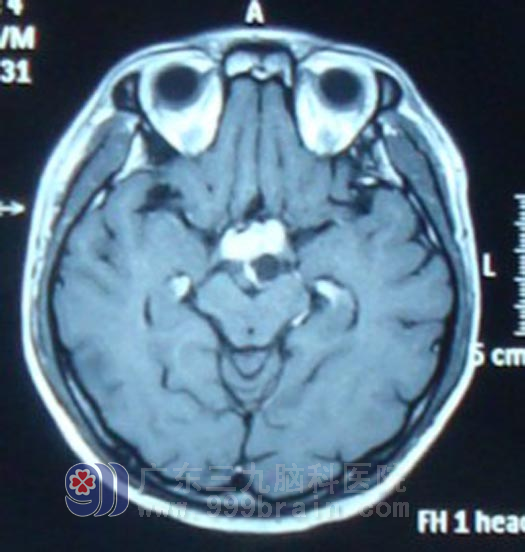

经人介绍,6月20日,小梁在家人陪同下来到广东三九脑科医院肿瘤综合治疗中心就诊。该中心蔡林波主任在了解小梁病史时发现,他除了视力下降(左眼视力0.1,右眼视力0.2)、视野发生改变外(双眼颞侧及上下侧视野缺损),近2个月以来还出现了多饮多尿现象,结合其影像学资料,蔡林波主任高度怀疑小梁患的是生殖细胞瘤,但确诊仍需要更多的临床资料。于是,抽取小梁的脑脊液进行化验检查,结果示HCG(人绒毛膜促性腺激素)值高出正常值10多倍,AFP(甲胎蛋白)也高于正常,这进一步证明小梁所患脑瘤为生殖细胞瘤的可能性极大。鉴于生殖细胞瘤首选放射治疗,蔡林波主任首先为小梁制定了定位适形诊断性放疗方案,放疗10Gy后,复查头颅MR显示肿物较前明显缩小,确诊为生殖细胞瘤。遂开始予全脑全脊髓放疗,完成54Gy后复查头颅MR显示肿瘤基本消失。患者症状明显改善,多饮多尿症状减轻,患者左眼视力恢复至0.4,右眼视力0.5。

放疗10Gy后